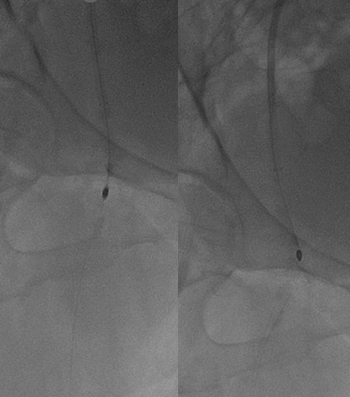

Procedural Step

An antegrade approach was first attempted via left femoral access using an 8 Fr long sheath advanced to the right femoral artery. Despite multiple manipulations, the wire and microcatheter failed to cross the calcified lesion at the superficial femoral artery ostium. The wire could engage the plaque but was unable to advance through the dense calcium. A retrograde approach was then established by puncturing the proximal superficial femoral artery under ultrasound guidance. The connection between the retrograde and antegrade wires was confirmed under orthogonal fluoroscopy. Using a rendezvous technique, the retrograde wire was advanced into the antegrade guiding catheter and externalized through the contralateral sheath, creating a continuous guidewire pathway.After wire externalization, sequential intraplaque and extraplaque rotational atherectomy were performed to modify both deep and superficial calcium. This ablation provided effective vessel preparation using a small burr size, improving compliance while minimizing procedural risk. Intravascular lithotripsy was subsequently performed to further optimize vessel expansion.Final high-pressure dilation achieved full luminal gain, followed by drug-coated balloon angioplasty as the definitive therapy. The final angiogram demonstrated excellent vessel expansion, preserved bifurcation flow, and no evidence of dissection, perforation.